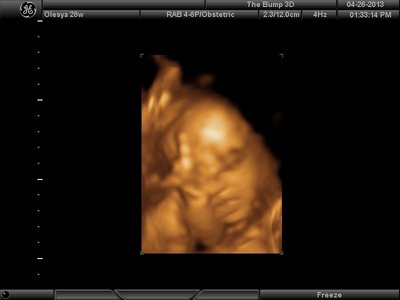

А я вчера на 3Д УЗИ ходила. Моя звезда закрывалась в еми 4мя конечностями. Просто пополам сложилась и спала себе сладко. УЗИстка провела со мной час, кое-как расшевелили маленькую, но ручка была постоянно на мордашке и засыпала она почти сразу снова. Я и на мяче прыгала и живот трясла. В конце более-менее фото вышли, но качество меня не порадовало. Возможно фри оф чардж еще раз переделают. Со средней фотки были отличного качества, а эти сплошное разочарование. Вот тут что-то более-менее еще. Главное пальчик оттопырила так смешно, мол минуточку. Вообще немного жутковатые фотки..хаха

| Вложения: |

|  image.jpg [ 47.86 КБ | Просмотров: 1193 ]